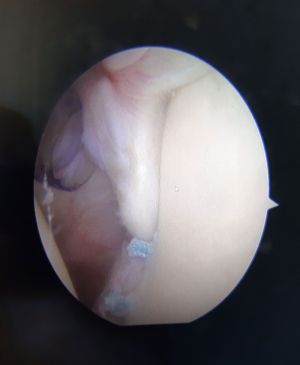

Bei der erstmaligen Luxation kann in der Regel ein arthroskopischer Eingriff durchgeführt werden. Hierbei wird das Labrum mit Nahtankern wieder am Knochen refixiert.

Bei bereits vorhandenem Knochenverlust nach oftmaligen Luxationen ist dies meist nicht mehr möglich. Hier muss ein Knochenaufbau mit körpereigenem Knochen erfolgen, um die Stabilität des Schultergelenkes wiederherzustellen (Latarjet, bzw. J-Span).